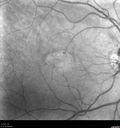

Macular Telangiectasis - Very Mild474 views52 year old female with normal vision and suspicious OCT referred. Multimodal imaging shows very mild mactel (loss of macular pigment, ring on multicolor image and very mild OCT findings)     (0 votes)